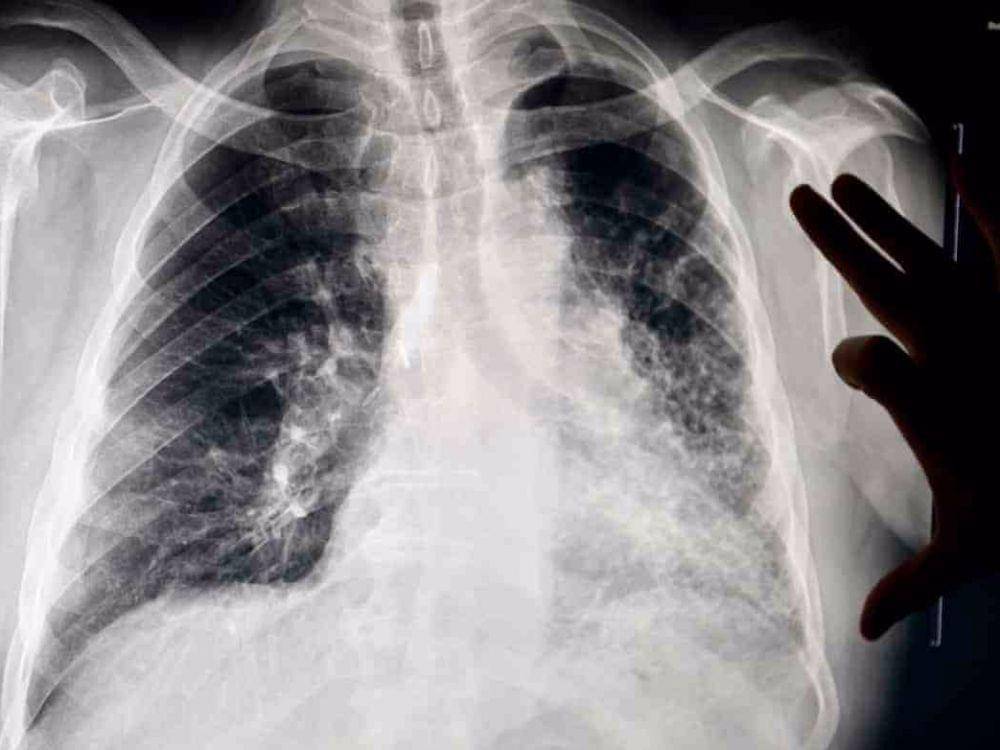

Menghirup udara kotor dalam jumlah banyak dan paparan terus-menerus bakal menyebabkan gangguan kesehatan pada sistem pernapasan. Berikut ini adalah beberapa masalah kesehatan yang bisa muncul akibat terlalu banyak menghidup debu atau udara kotor.

3. Pneumokoniosis

Mirip silikosis, pneumokoniosis muncul akibat terlalu banyak menghirup udara yang berpartikel debu dan menyebabkan kerusakan pada paru-paru. Dilansir John Hopkins Medicine, ada beberapa tipe pneumokoniosis. Salah satunya adalah paru-paru hitam yang muncul karena menghirup udara dengan debu batu bara.

6. Emfisema

Emfisema adalah penyakit kronis pada sistem pernapasan akibat adanya kerusakan pada alveolus, kantong udara kecil yang ada di paru-paru. Paparan asap rokok, debu lingkungan, dan polusi udara dalam jangka lama adalah penyebab utama terjadinya masalah ini. Mengingat emfisema tidak bisa disembuhkan dan hanya bisa diredakan, kamu perlu mewaspadainya.